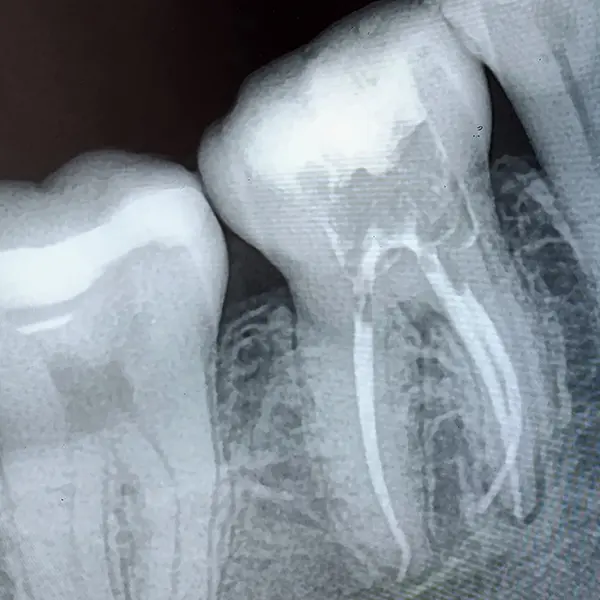

Контроль: рентгеновские снимки